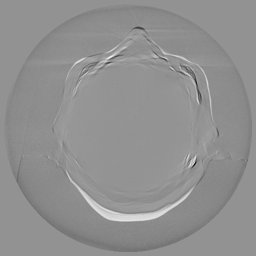

The results for simulated noisy data are shown in Fig. 2. The first and third rows display two representative slices from the test set, and the second and fourth rows present the corresponding error maps. The traditional WCE method suppresses cupping artifacts and recovers some missing anatomical structures but still shows noticeable deviations from the ground truth. Predictions from the four diffusion-based models demonstrate a markedly improved ability to restore anatomical structures. Among them, cDDPM fails to fully reconstruct the patient bed and retains residual noise in its outputs. This noise is attributable to an incomplete reverse denoising process rather than residual Poisson noise, as evidenced in our noise-free experiments (Fig. 5 in the Appendix). PatchDiffusion, diffusionGAN, and I2SB achieve similar visual quality, with I2SB producing the cleanest and most consistent reconstructions.

Quantitative results in Tab. V further confirm I2SB’s superiority over conventional deep learning methods such as FBPConvNet and Pix2pixGAN across RMSE, PSNR, and SSIM. Compared to other diffusion models—including cDDPM, PatchDiffusion, and cLDM—I2SB delivers higher image quality, while diffusionGAN achieves comparable quantitative performance. However, I2SB demonstrates a significant advantage in inference efficiency, as summarized in Tab. IV.